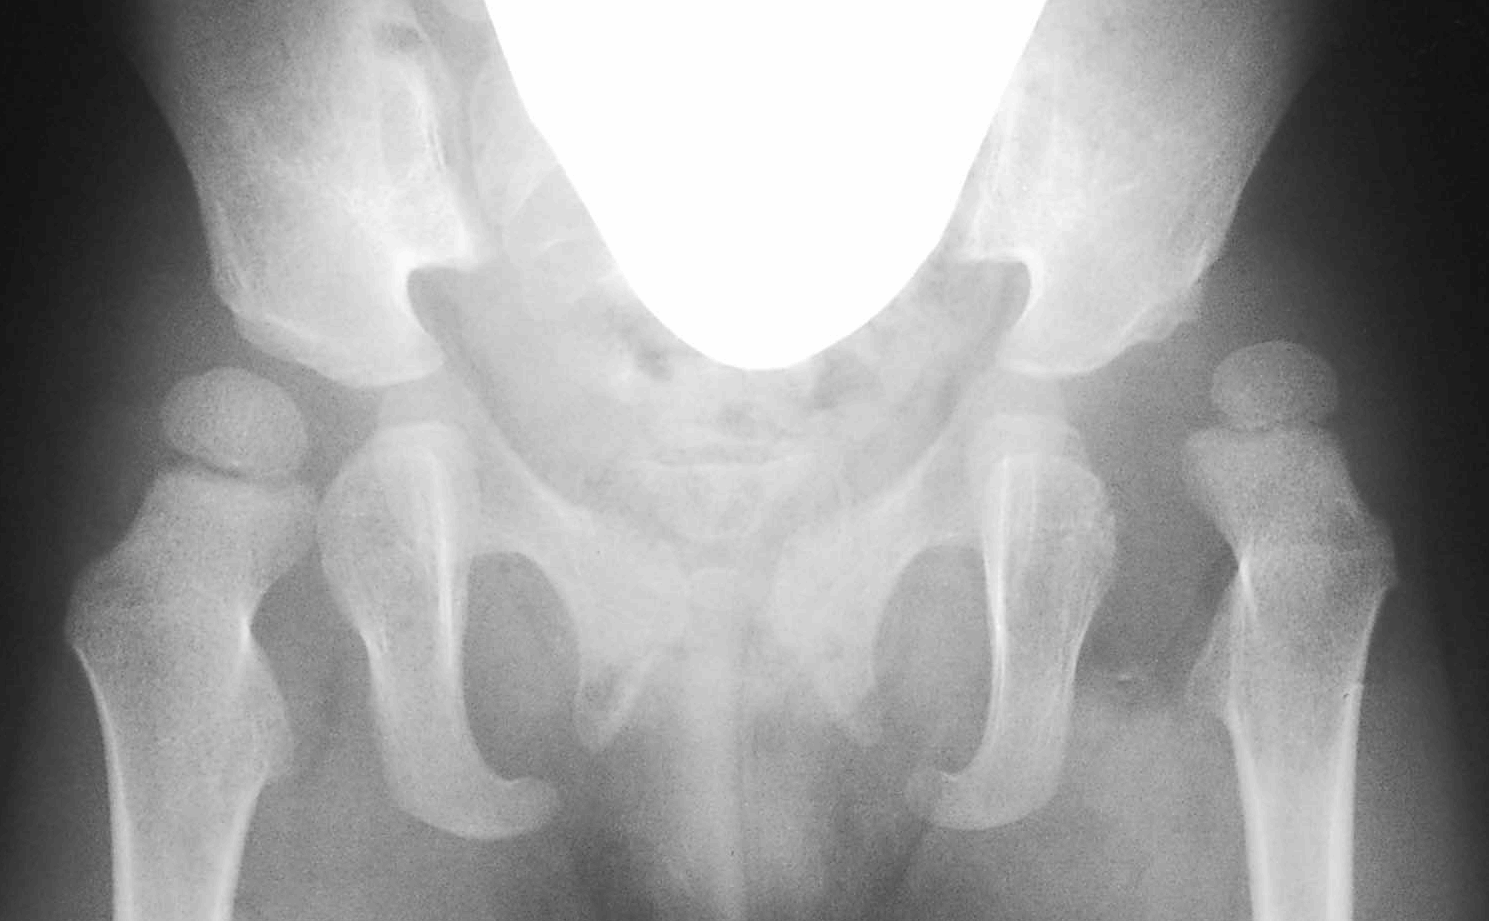

2歳女子、他院にて整復を行ったが、初診時、写真のごとく立位で不安定な関節であった。

しかし、股関節を外転かつ内旋すると骨頭と臼蓋の関係は改善した。